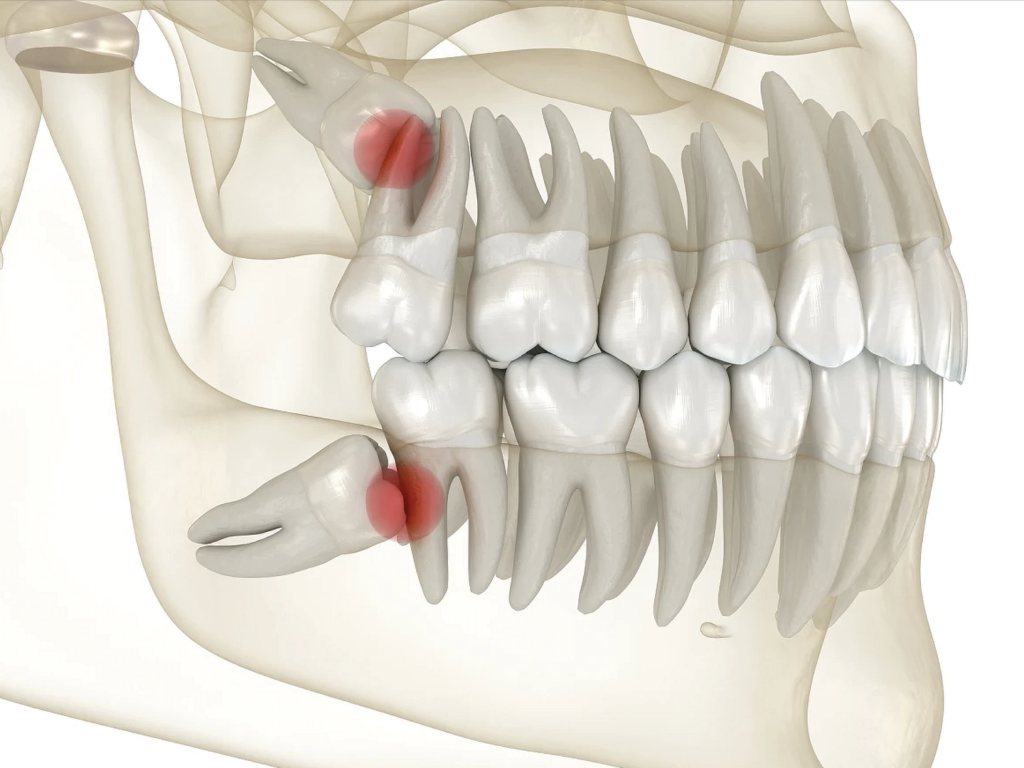

Dent de sagesse

Prise en charge des dents de sagesse gênantes ou à risque (douleur, inflammation, manque de place), avec protocole et suivi.

- Une dent de sagesse douloureuse, enflammée ou incluse

Dent de sagesse : faut-il toujours l’enlever ?

-Non. On l’enlève surtout si elle crée douleur, inflammation, carie, manque de place ou risque sur les dents voisines.